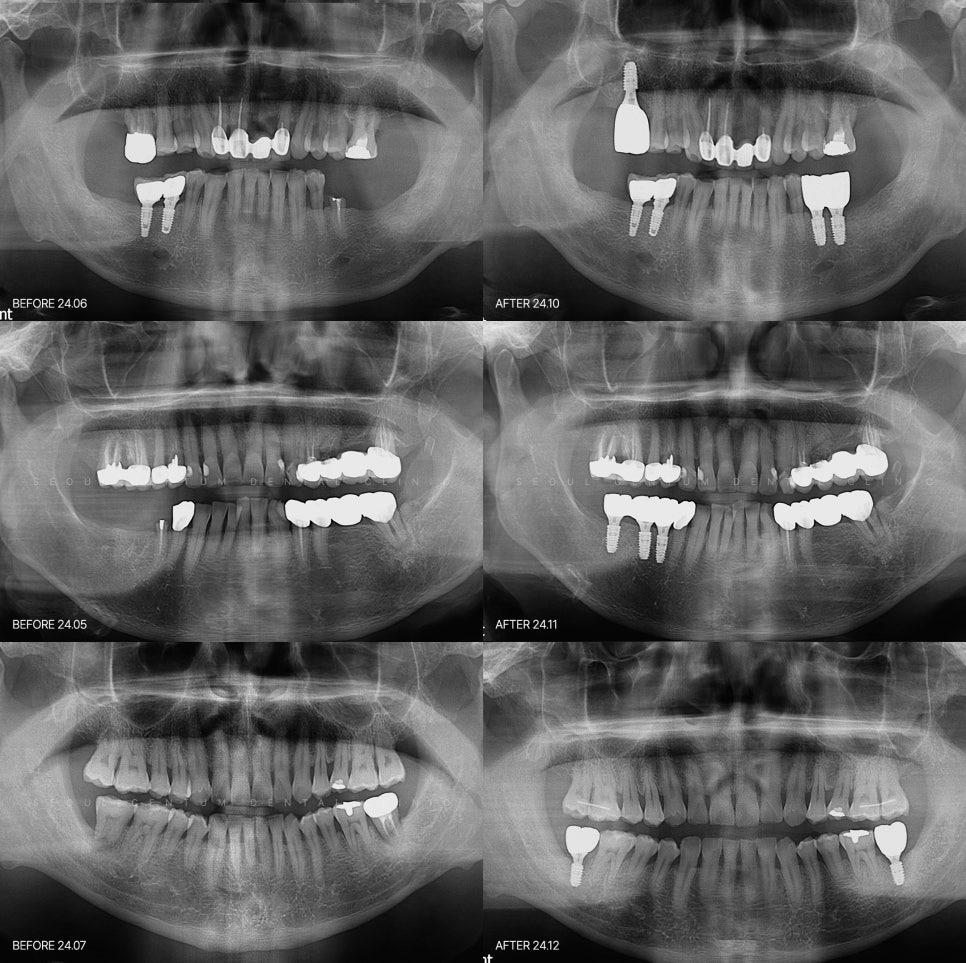

임산부임플란트 다르게 접근해야만 합니다

임산부 임플란트의 경우 일반적인

임플란트와 똑같이 진행되지는 않습니다.

꼭 필요한 단계만 최소한의 마취로

불필요한 촬영 및 약물은 최대한

배제를 하고 진행을 하게 되고요.

대부분의 경우 완성까지 한번에 간다기보다

단계적으로 나누어서 진행하는 방식을

선택하게 되는데요.

당장 급한 통증이나 염증을 잡는것을

우선으로 진행을 하고요.

본격적인 임플란트 식립은

출산이후로 미룬다던지 하는 부분입니다.

임신중에 부담을 줄이면서

출산 후 바로 임플란트를 할 수 있게

준비과정을 마쳐놓는 방식이라고

볼 수 있겠습니다.